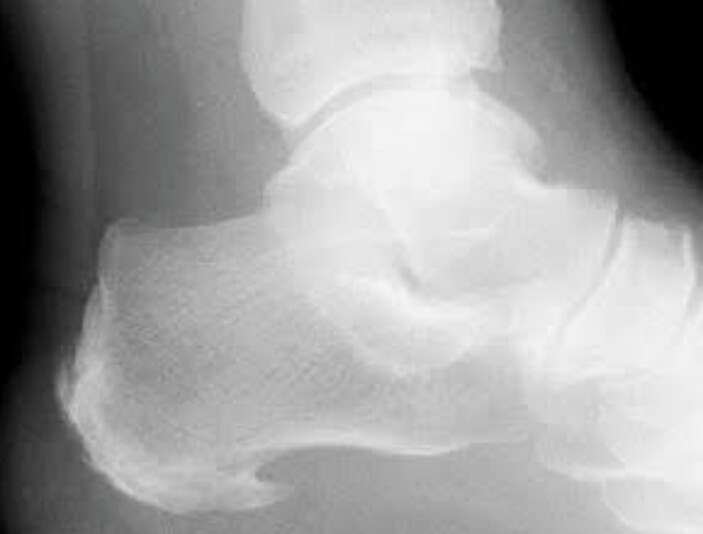

TREATMENT FOR CALCANEAL SPUR